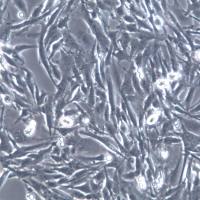

很多生物医药的研究都采用培养细胞来进行, 这些细胞可能是从细胞库 (如美国 ATCC,American Type Culture Collection) 得来,也可能是受赠于其它研究人员,尤其在中国,目前细胞的传播太复杂,无序,很多都不是通过正规途径获得,如友情赠送等。

据统计,约有 30% 细胞系被交叉污染或错误辨识,因使用了交叉污染或错误辨识的细胞会导致研究结论错误、结果不可重复、临床细胞治疗失败等。不仅浪费大量时间、精力和金钱,还可能造成不可挽回的灾难性后果。为此,很多细胞库现在都要对提交来的细胞系进行鉴定,并对细胞系之间的交叉污染进行监测。